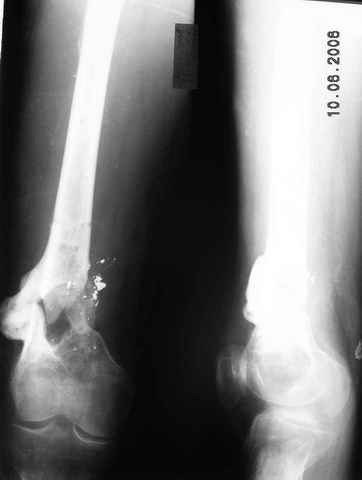

Возможно, проф. Лазарев предложит другой вариант, а в наших условиях мы бы закрыто заштифтовали бы бедро антеградно. Устранили бы варус, используя голень как рычаг, вероятнее всего, даже дистрактор не понадобился бы. В приницпе, можно и ретроградно ири наличии движений в колене, но варус будет труднее устранить - можно и предварительно аппаратом в таком случае.